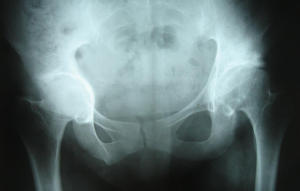

Η φυσική ιστορία μιας καθυστερημένα διαγνωσμένης και θεραπευμένης αμφοτερόπλευρης ΑΝΙ και οι συνέπειες αυτής της καθυστέρησης παρουσιάζονται στις εικόνες 1-4.

Η ασθενής υπεβλήθη καθυστερημένα σε ανοικτή ανάταξη ισχίων άμφω σε ηλικία 5 ετών (εικόνα 1). Στην εικόνα 2 φαίνονται τα αναταγμένα αλλά σαφώς παθολογικά ισχία. Στην εικόνα 3 τα ισχία παρουσιάζουν εικόνα πρώιμης οστεοαρθρίτιδας ενώ στην εικόνα 4 η ασθενής πάσχει από βαριά οστεοαρθρίτιδα των ισχίων άμφω με άλγος ηρεμίας. Η πραγματοποίηση ολικών αντικαταστάσεων αμφότερων των ισχίων είναι μονόδρομος.

Εικόνα 4: 2010, 33 ετών, βαριά οστεοαρθρίτιδα ισχίων άμφω, άλγος ηρεμίας, προγραμματισμός για ολική αρθροπλαστική ισχίων